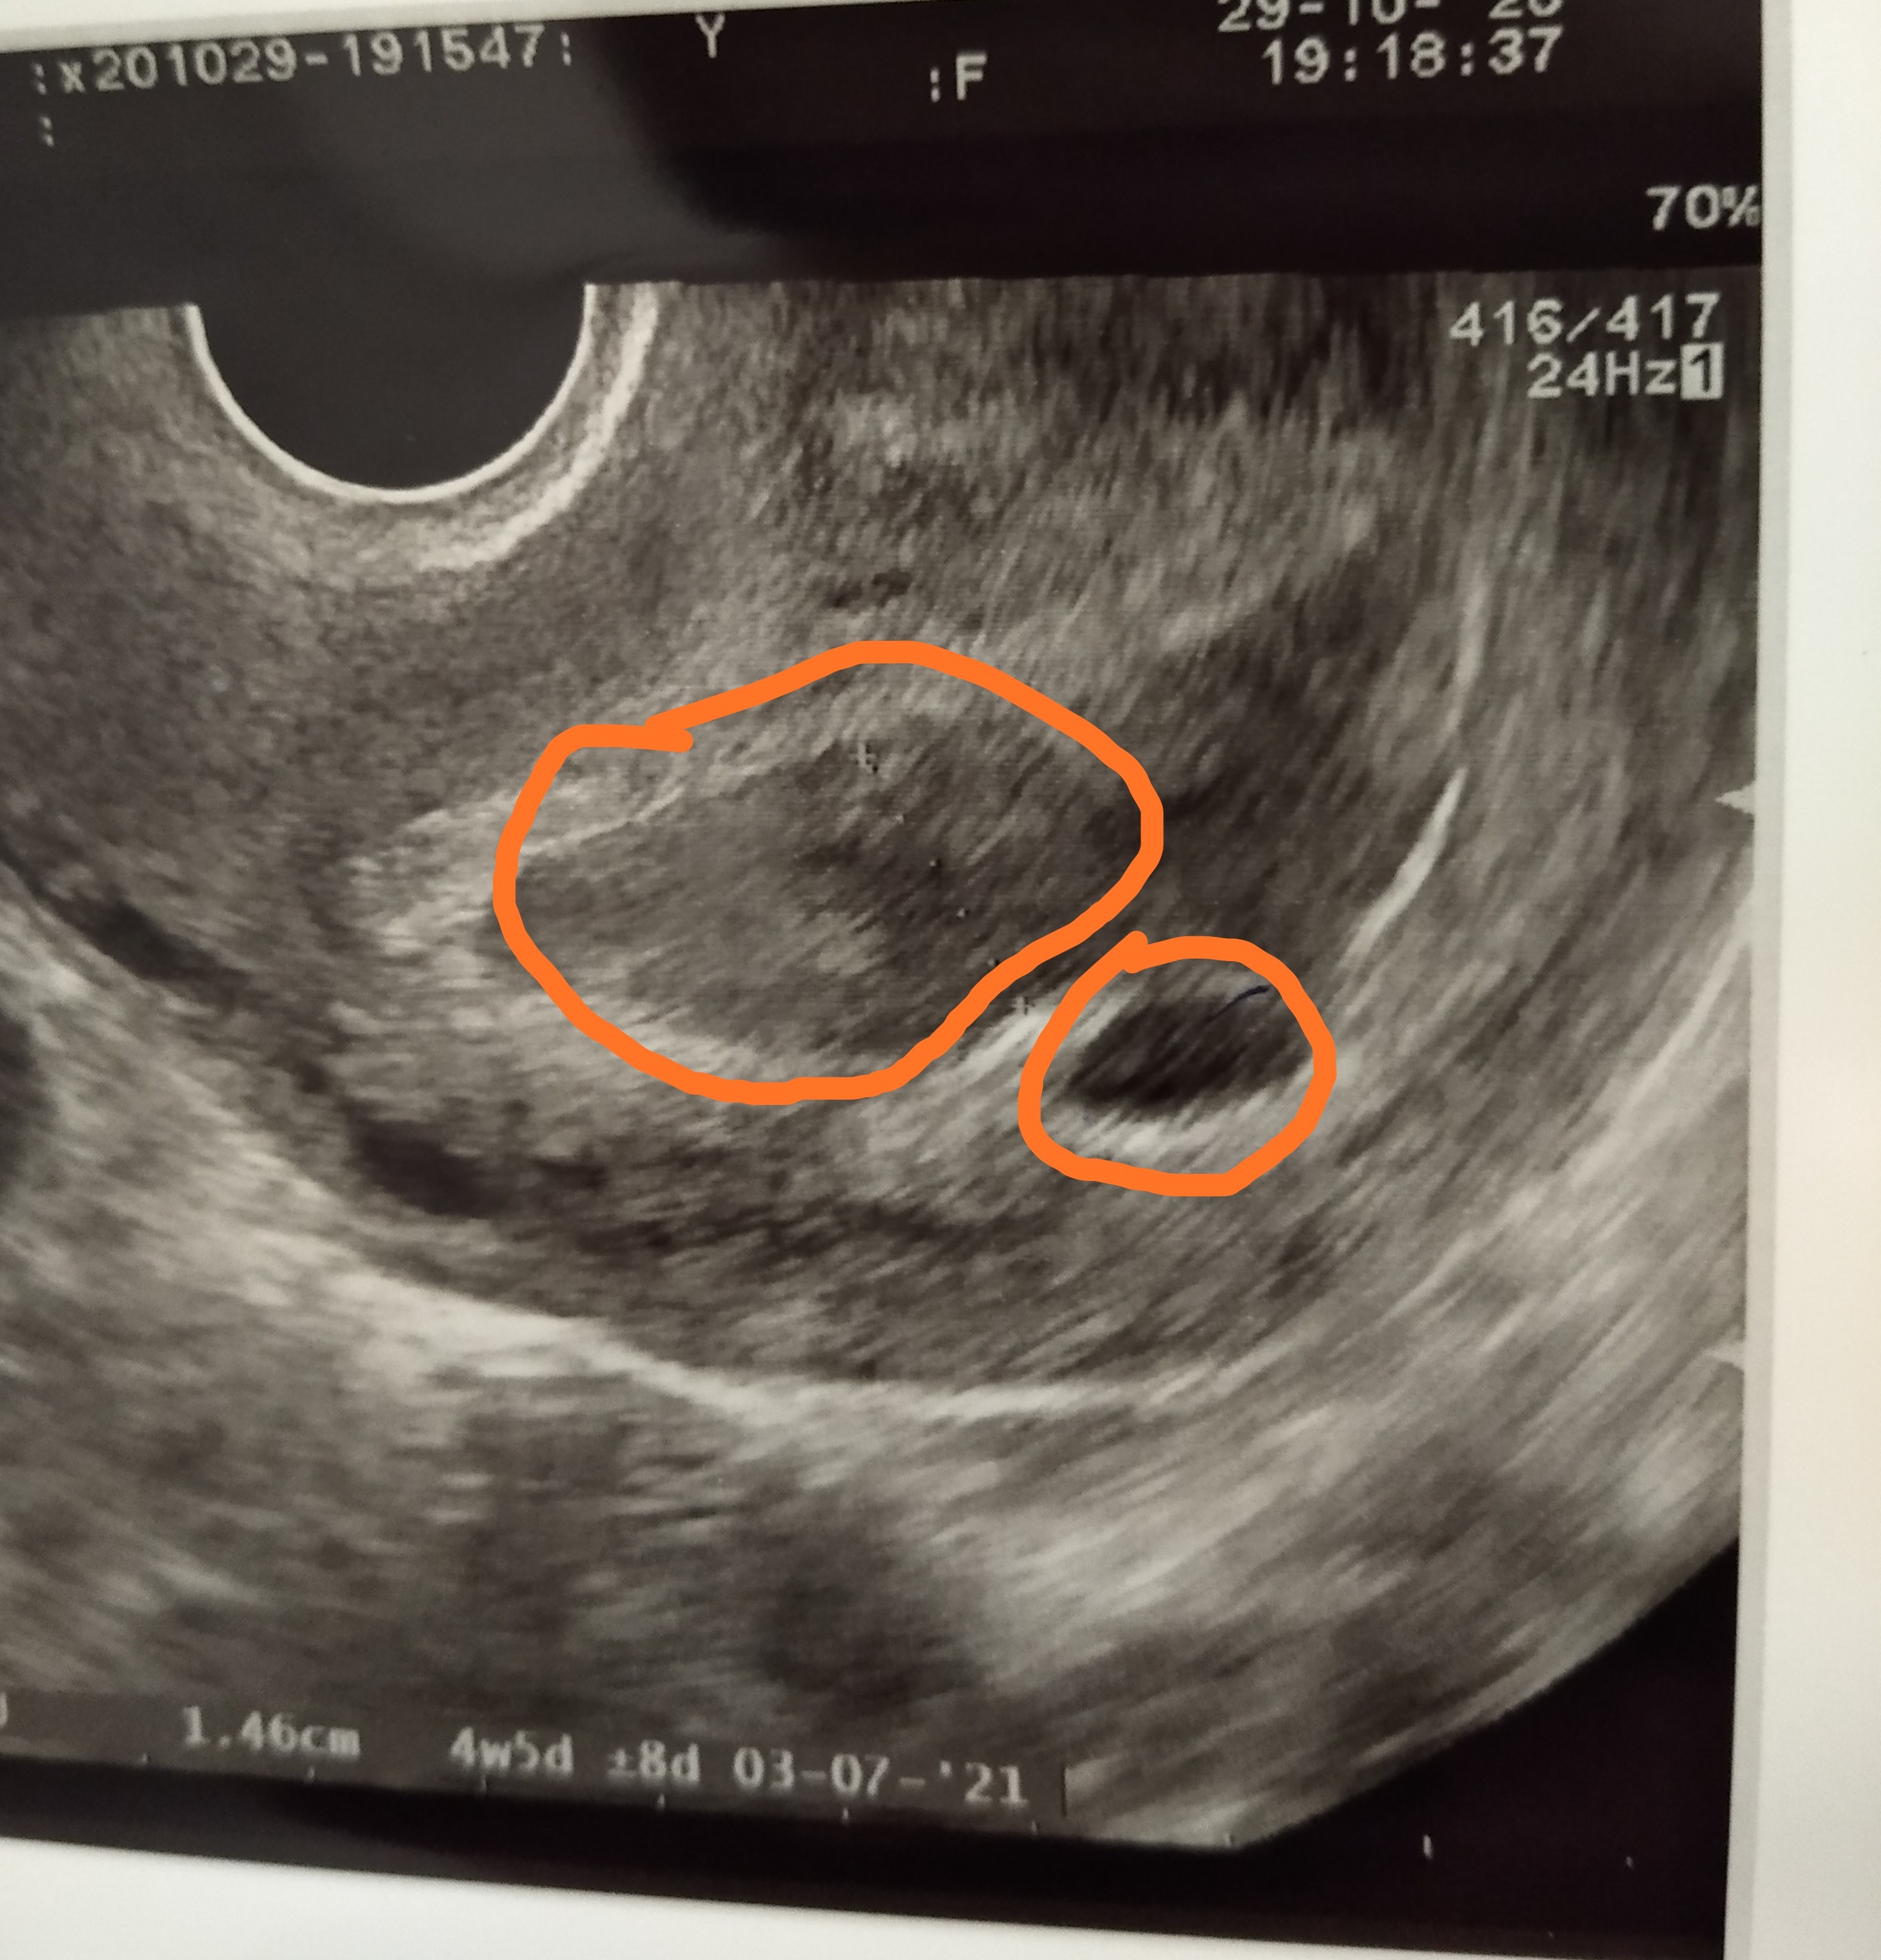

Dziewczyny, co może oznaczać ta rozlana krew? Czy to jest właśnie krwiak? Mój lekarz nie nazwał tego. Na zdjęciu USG jest obok pęcherzyka ciążowego 😔

Hej dziewczyny byłam u lekarza, w badaniu USG powiedział, że krwiak jest dużo mniejszy niż poprzednio, czyli się wchłania. Pęcherzyk jest ale przy pobraniu pomiaru lekarz stwierdził, że wielkościowo wygląda podobnie jak 2 dni temu, a on chciałby żeby rósł. Jak zapytałam o szansę powiedział, że nie chce jeszcze nic odpowiadać, mam dalej brać Duphaston 3x1 i oszczędzać się. Kolejna wizyta we wtorek po południu. Pęcherzyk dziś miał 1,38cm. Czy może się jeszcze udać?